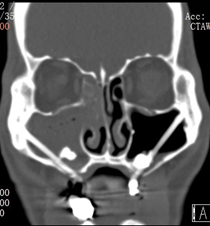

鼻内镜检查单侧中鼻道脓性物(下图)

中鼻道脓性物流向鼻咽部

鼻内镜检查中鼻道可见脓性鼻涕、水肿或息肉